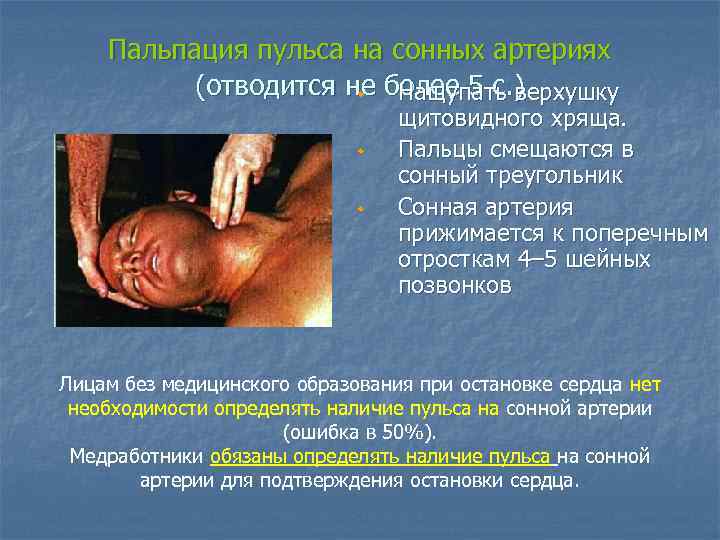

Пальпация пульса на сонных артериях (отводится не более 5 с. ) w Нащупать верхушку w w щитовидного хряща. Пальцы смещаются в сонный треугольник Сонная артерия прижимается к поперечным отросткам 4– 5 шейных позвонков Лицам без медицинского образования при остановке сердца нет необходимости определять наличие пульса на сонной артерии (ошибка в 50%). Медработники обязаны определять наличие пульса на сонной артерии для подтверждения остановки сердца.